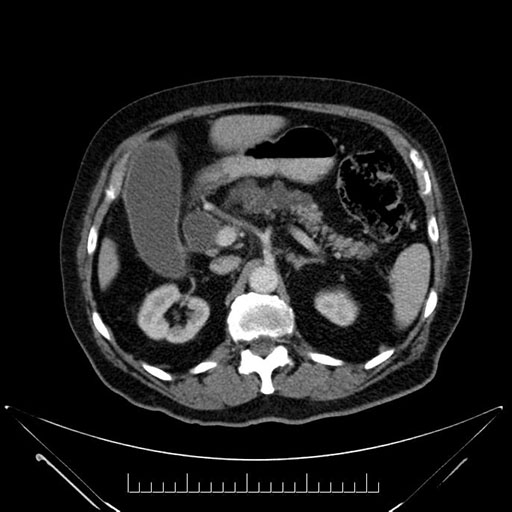

Whipple (pancreaticoduodenectomy) [case 7]

Look through the patient's CT scan to identify any areas of concern for the necessary procedure.

Axial - 3 months prior

Imaging analysis

Based on your CT findings, which issue(s) would give reason for "planned slowing down moment(s)" in this case?

Considering a standard Whipple procedure, what step(s) of the operation would you do differently in this case?